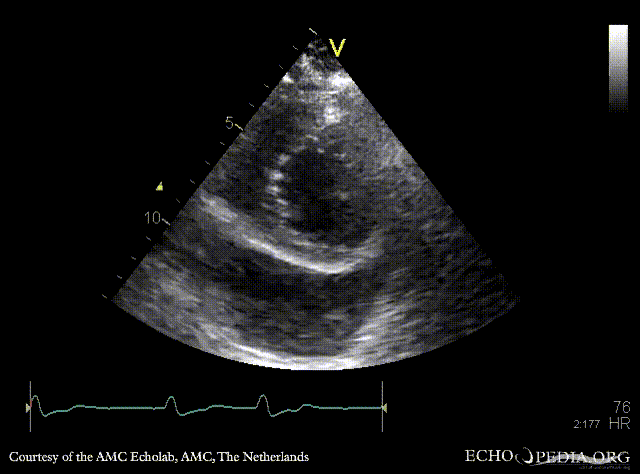

PLAX: dilated coronary sinus A4CH with Color Doppler: severe tricuspid regurgitation